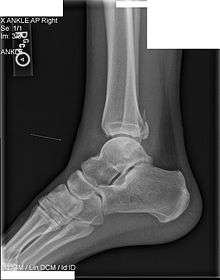

The Maisonneuve fracture is a spiral fracture of the proximal third of the fibula associated with a tear of the distal tibiofibular syndesmosis and the interosseous membrane. There is an associated fracture of the medial malleolus or rupture of the deep deltoid ligament. This type of injury can be difficult to detect.

Posterior malleolus fracture